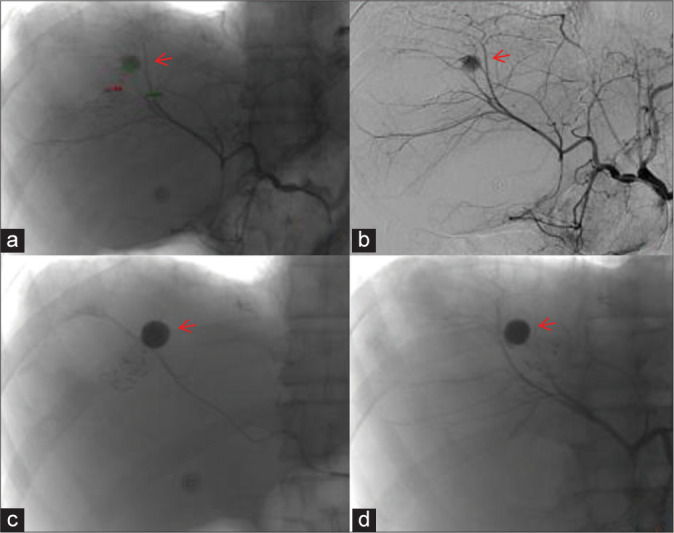

Results: A total of 32 pseudoaneurysms were embolized in 31 patients with peripheral pseudoaneurysms. All pseudoaneurysms originated from visceral arteries. Among them, 29 pseudoaneurysms were embolized with medical adhesive alone, and three pseudoaneurysms were embolized with coil-assisted medical adhesive. After endovascular embolization with medical adhesive, all pseudoaneurysms were successfully embolized. Technical success was 100%. All patients experienced cessation of bleeding after endovascular embolization with medical adhesive, and there were no serious post-operative complications. Clinical success was 100%. During the follow-up period, two patients experienced recurrent bleeding but no pseudoaneurysm recurrence was observed.

Abstract Image